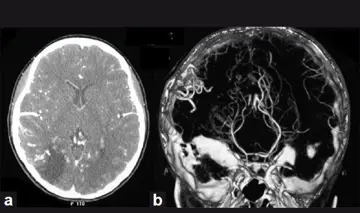

درمان AVM پاره نشده مغز